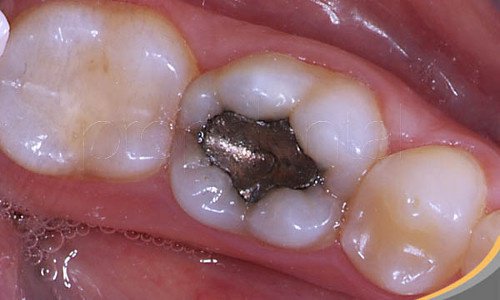

Amalgam Dolgu Nedir?

Amalgam çeşitli metallerden yapılan gri renkli bir maddedir, genellikle içinde cıva bulunur, amalgam da dişteki boşlukları doldurmak için çoğu dişçi tarafından kullanılır.

Amalgam dolgu 120 ile 570 mg arasında cıva içerir, tükürük, mide asidi, yüksek sıcaklık ve başka sebeplerden dolayı da bu cıva zamanla dışarı salınır.

Bu, gün geçtikçe vücut tarafından emilen cıva buharı çıkarır, dolgular bu yüzden gün geçtikçe zehirli olmaya başlar.